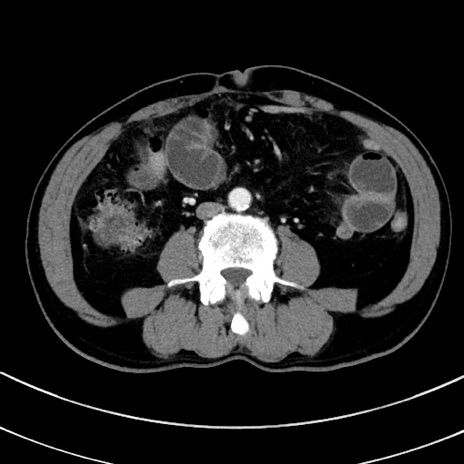

症例8(横断像)

【症例】 60歳代男性

【主訴】 黒色吐物

【現病歴】 4日前から嘔気自覚、2日前の朝食後にも嘔気あり、自分で手で嘔吐反射起こし嘔吐したところ血が混ざっていたため受診。

【既往歴】 5年前汎発性腹膜炎を伴う急性虫垂炎で手術、高血圧、前立腺肥大症、高脂血症

【身体所見】 腹部正中に手術癩痕あり 腹部平坦・軟圧痛なし膨満感あり

【データ】WBC 8400、CRP 4.54